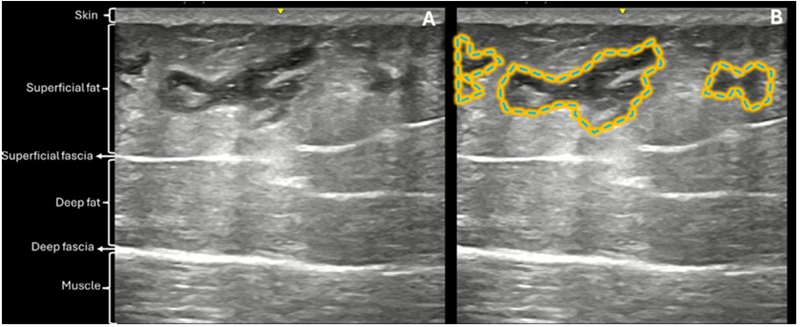

Standardized 2D and 3D imaging demonstrated a clear increase in buttock volume and improvement in overall contour. Common aesthetic concerns, including hip dips and deep infragluteal folds, showed visible correction. Ultrasound imaging confirmed accurate placement of the filler within the subcutaneous layer. Over time, the injected HA gradually integrated with surrounding adipose tissue and underwent partial resorption, without evidence of migration, nodule formation, or fibrosis.

Figure 8–10 | Ultrasound evolution of hyaluronic acid filler over time. Immediate post-treatment images show well-defined, anechoic filler deposits in the subcutaneous layer. At one month, surrounding tissue demonstrates expected reactive changes consistent with early integration. At one year, blurred margins and reduced echogenic contrast indicate partial resorption and incorporation into native tissue, correlating with sustained contour support.